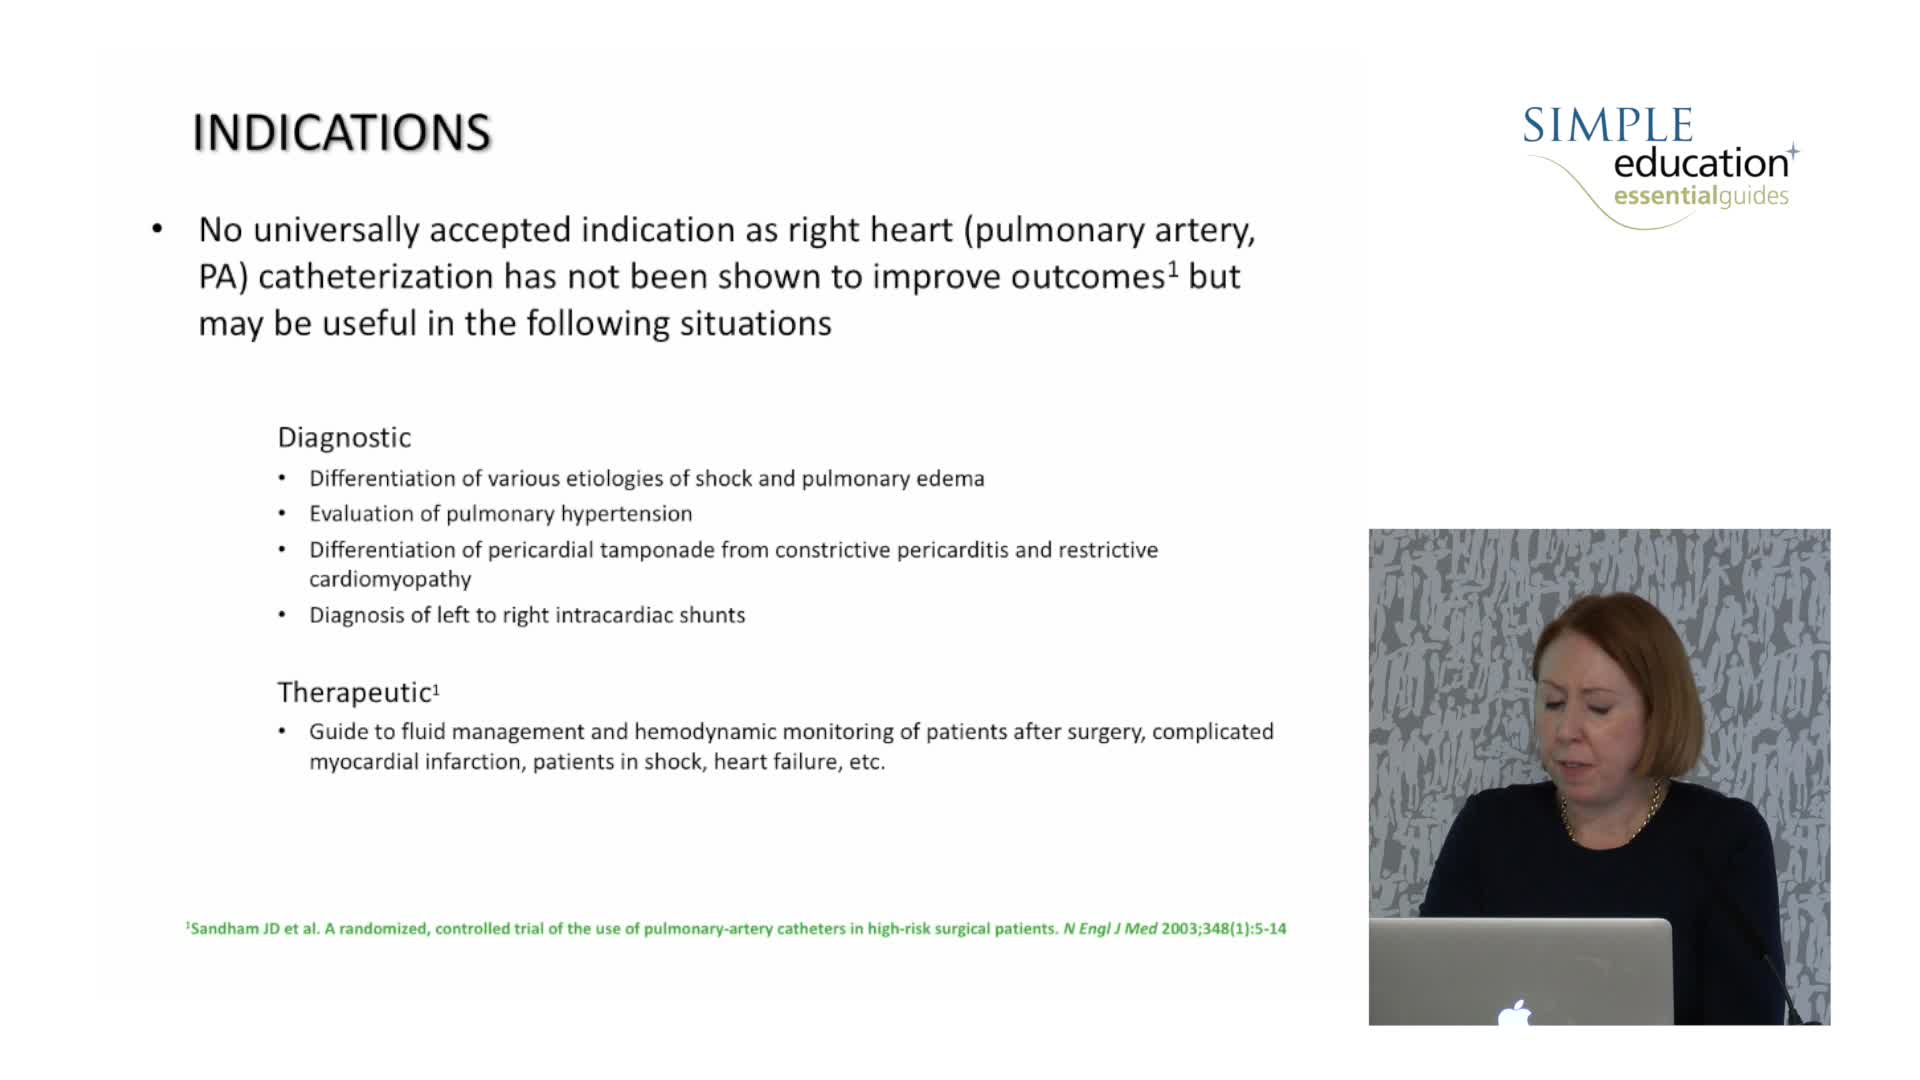

Prevention of Contrast Induced Nephropathy: Fact, Fiction and Fantasy - Christopher Baker